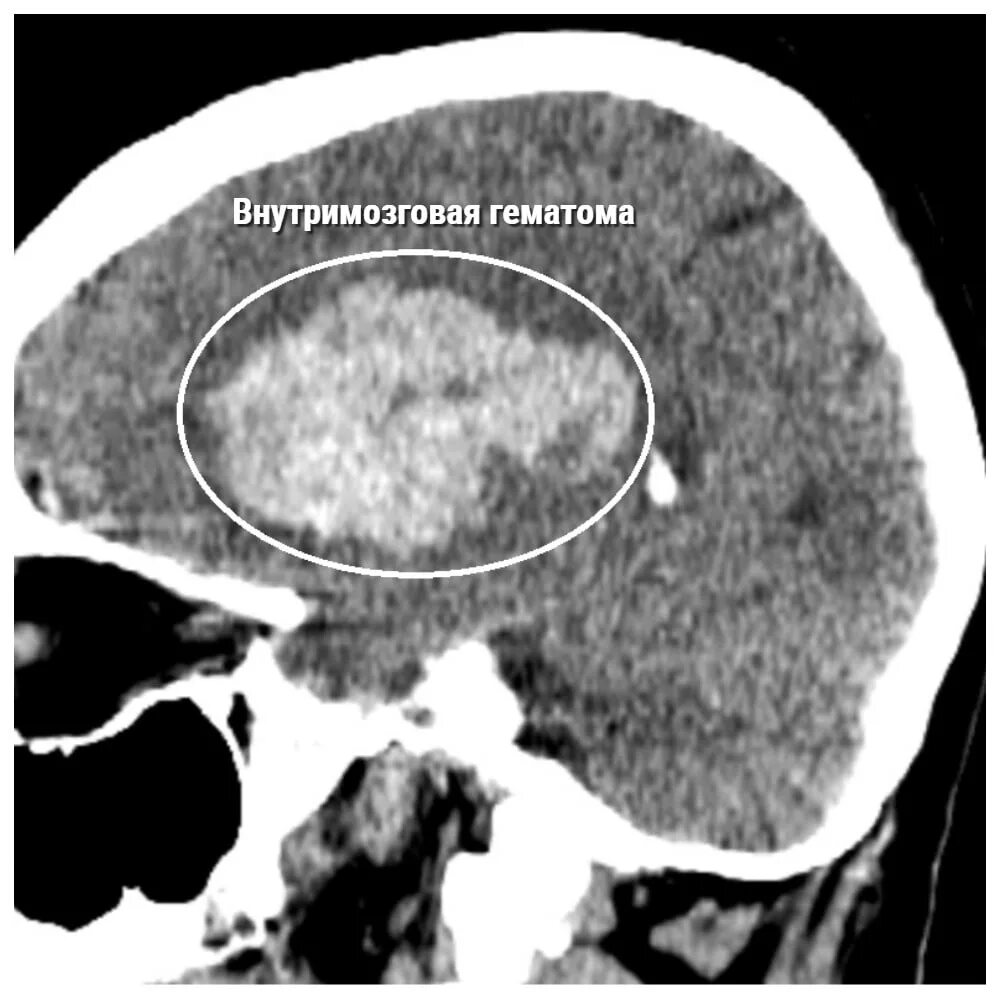

Объем гематомы на кт